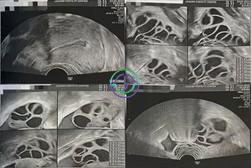

促排第 8 天 — 多个卵泡已逐渐发育,尺寸渐渐增大

超声结果

右侧卵巢:卵泡大小 17,17,17,17,16,12,12,12,11,10,10 mm → 共 11 个卵泡

左侧卵巢:卵泡大小 17,16,16,15,15,14,14,13,12,11,10,10 mm → 共 12 个卵泡

促排第 10 天 — 多个卵泡已长大,但部分尚未成熟;继续用药

右侧卵巢:卵泡大小 18,18,18,17,17,14,14,14,13,13,12 mm → 共 11 个卵泡

左侧卵巢:卵泡大小 20,19,19,18,18,17,17,17,17,16,16 mm → 共 11 个卵泡

促排第 11 天 — 几乎所有卵泡已达目标大小;准备取卵

右侧卵巢:卵泡大小 21,20,20,21,19,19,19,18,18,18,17,16,15,14 mm → 共 14 个卵泡

左侧卵巢:卵泡大小 22,20,20,20,20,20,19,19,18,17,17,17,17,16 mm → 共 14 个卵泡

在本病例中,卵巢刺激反应良好。卵泡从最初的小尺寸逐渐发育,到第 11 天时已有大量卵泡达到适宜大小(18–22 mm)。雌激素水平也持续升高,提示卵泡已准备好接受触发针注射和取卵。